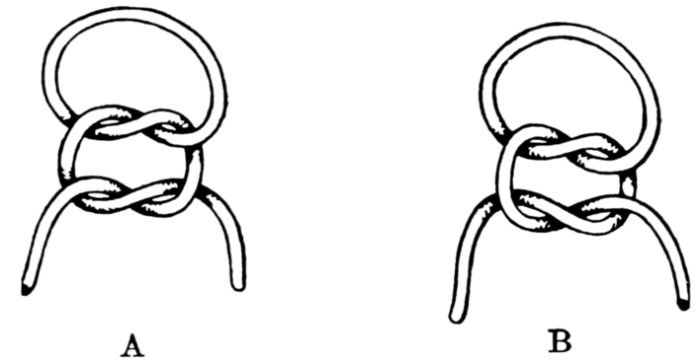

| 92. | Wrong and right method in tying knot in cord ligature | 272 |